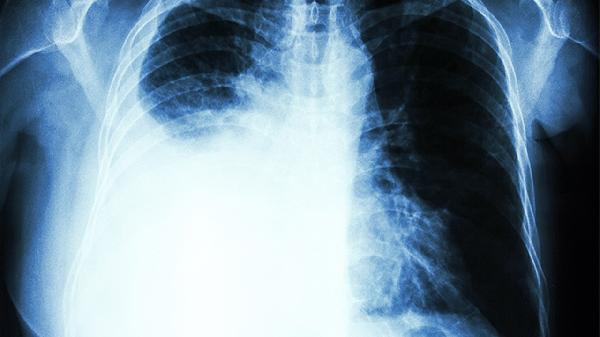

立体定向放疗适用于不能手术的早期患者,根治性放疗用于局部晚期病变。放射性肺炎是常见并发症,精准放疗技术可降低周围组织损伤。放疗常与化疗或免疫治疗联合应用。